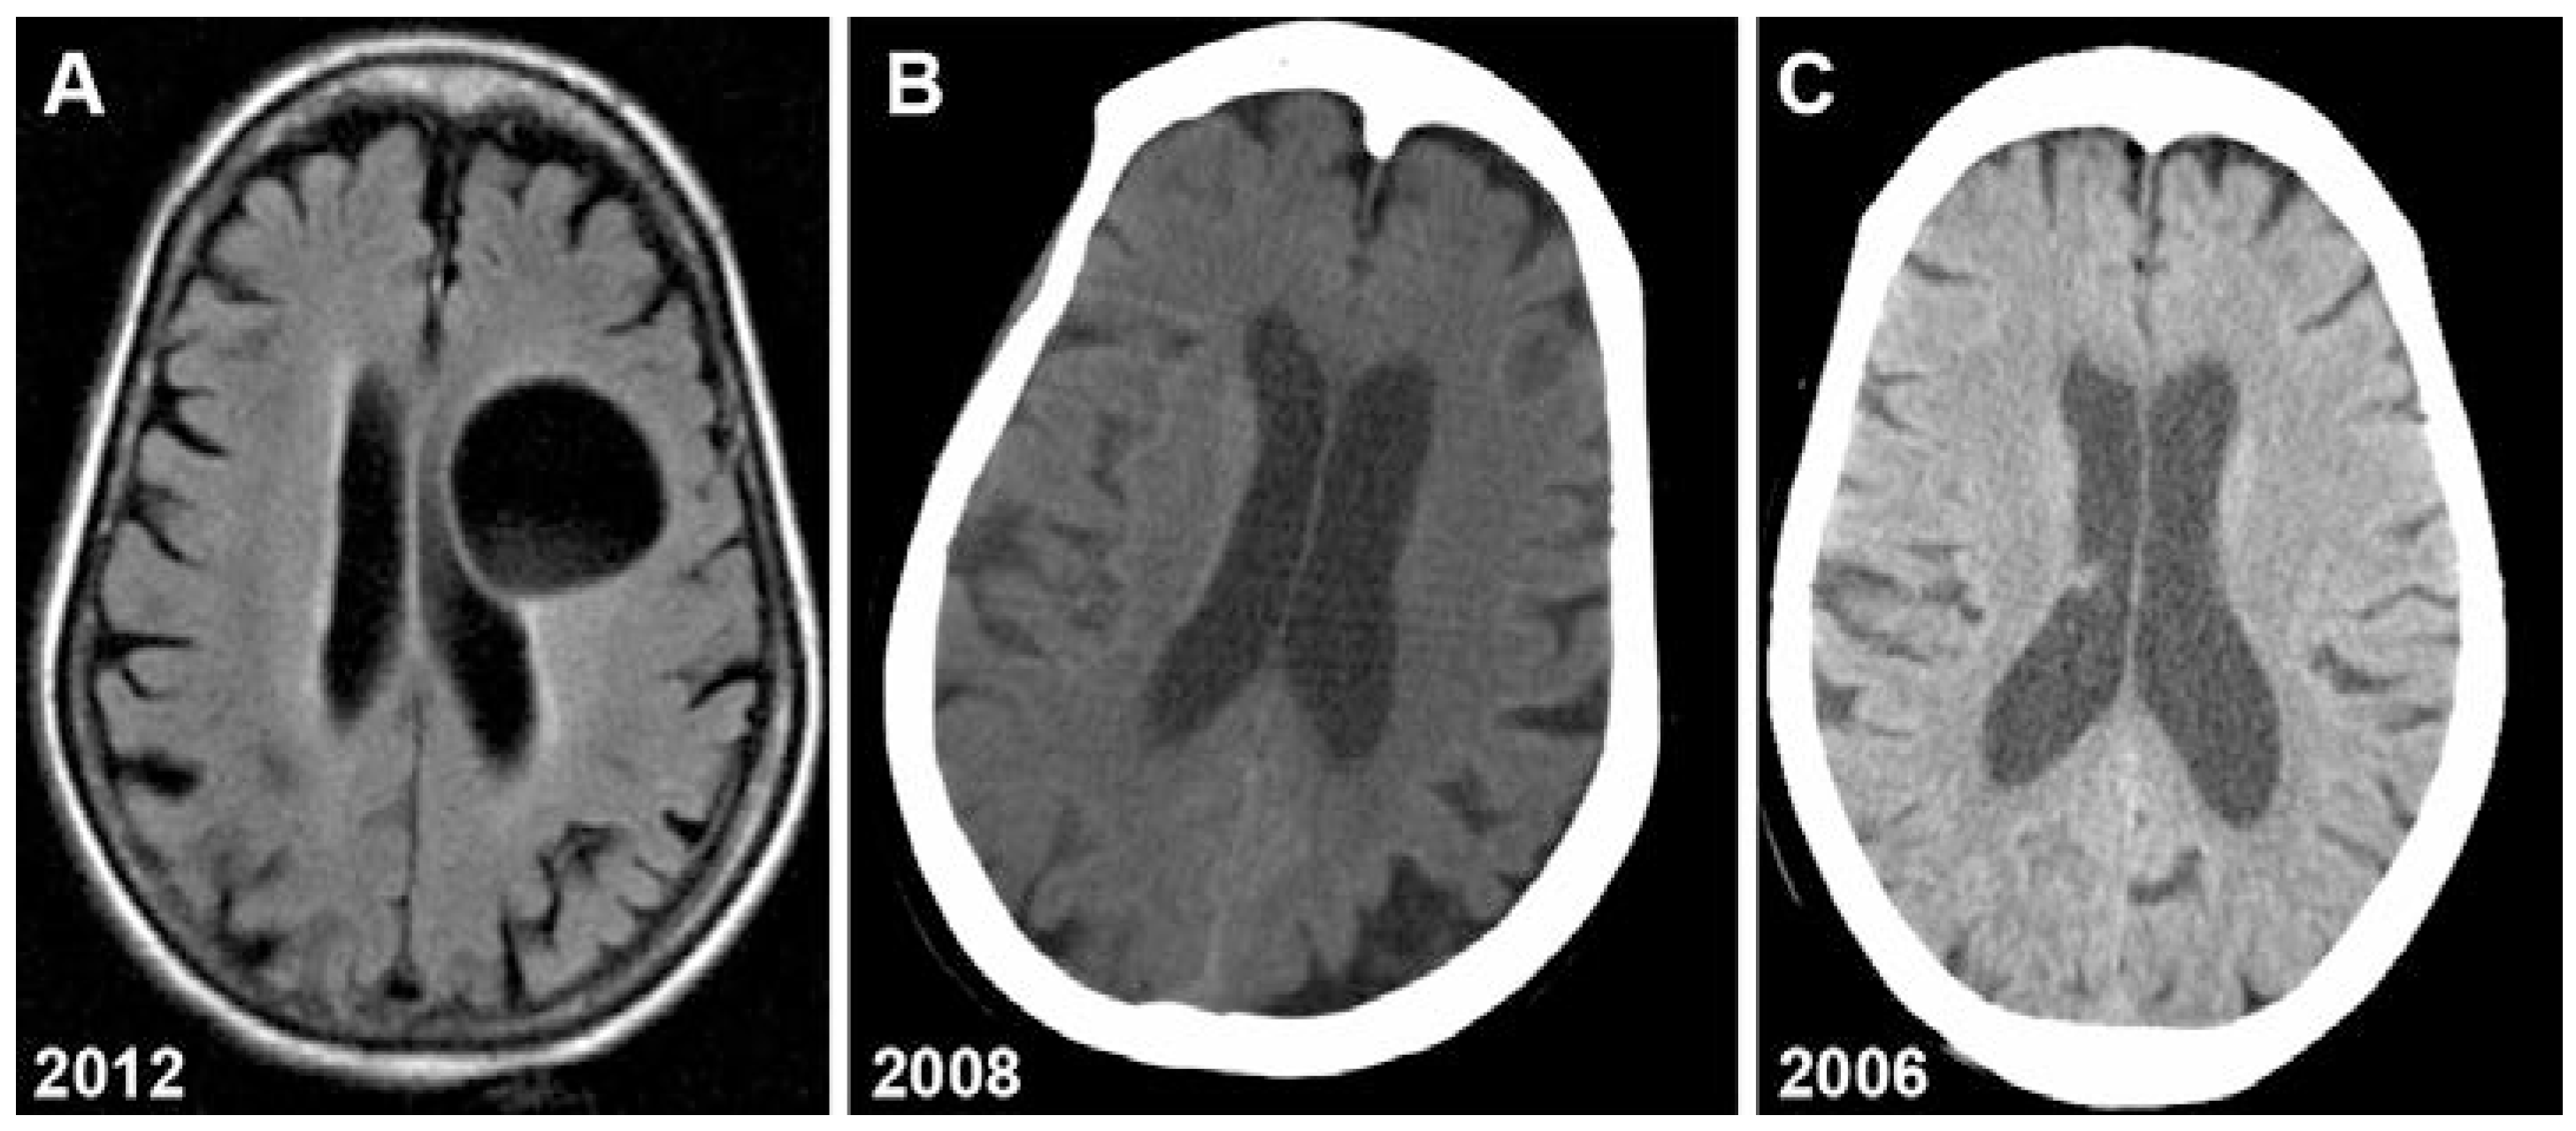

Magnetic resonance imaging (MRI) revealed a well circumscribed cystic lesion, with CSF density, measuring 4.5 × 3.7 cm (Figure 1A). This cyst compressed the frontal horn of the left lateral ventricle. There was no surrounding edema and the basilar cisterns were well preserved. A CT scan performed 4 years earlier showed a lesion of 7–8 mm in diameter (Figure 1B). This lesion was not visible on a head CT performed six years earlier (Figure 1C).

Figure 1.

Neuroimaging showing growth of hydatid cyst over 6 years. A: brain MRI (2012); B: head CT (2008); C: head CT (2006).

This type of lesion was consistent with a persistent hydatid cyst which had grown 5-fold in 4 years. Finally it was the classic imaging findings that confirmed our diagnosis of hydatid cyst.

The diagnosis of cerebral hydatid cyst disease depends on the probability of exposure combined with pathognomonic features on imaging. CT and MRI show spherical well-defined, thin-walled lesions without surrounding edema. Calcification and surrounding edema are rarely seen whereas these are commonly seen with cerebral alveolar echinococcosis. Ventricle compression is common [15]. MRI and CT scans characteristically show hydatid cysts as spherical, well circumscribed, thin-walled, non-enhancing lesions without peripheral edema (Figure 1A,B). There is usually no surrounding edema or CT enhancement.